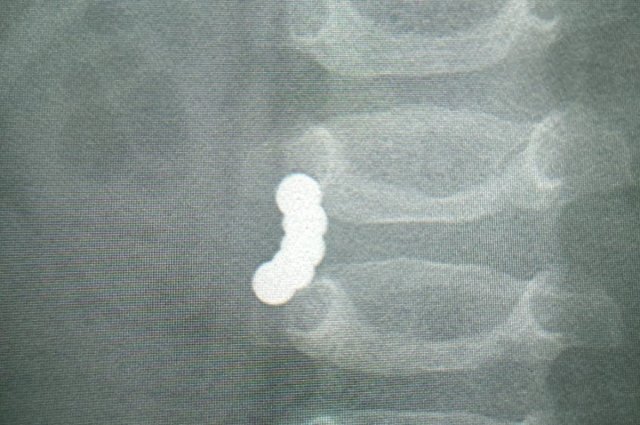

Томские врачи спасли годовалого мальчика, проглотившего пять магнитов из игрушки-конструктора